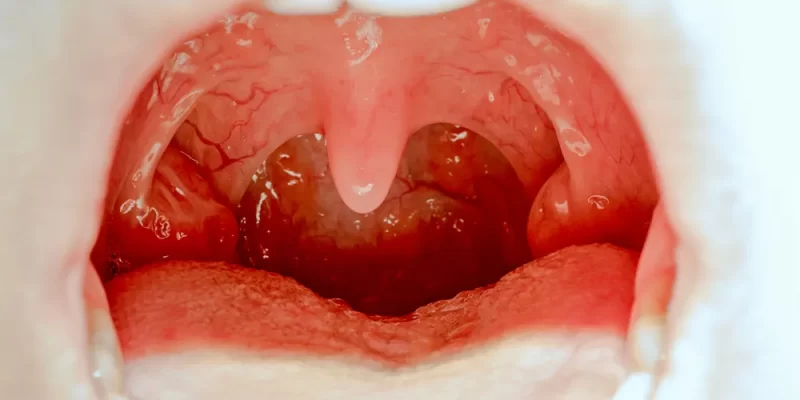

Tonsillectomy is a surgical procedure that removes the palatine tonsils—two lymphoid tissues located at the back of the throat. These tonsils help fight infections, but when they become chronically infected or enlarged, they can do more harm than good.

- Recurrent tonsillitis (7 or more episodes per year)

- Chronic sore throat

- Obstructive sleep apnea

- Difficulty swallowing

- Snoring due to tonsillar enlargement

- Recurrent peritonsillar abscess

- Breathing problems in children